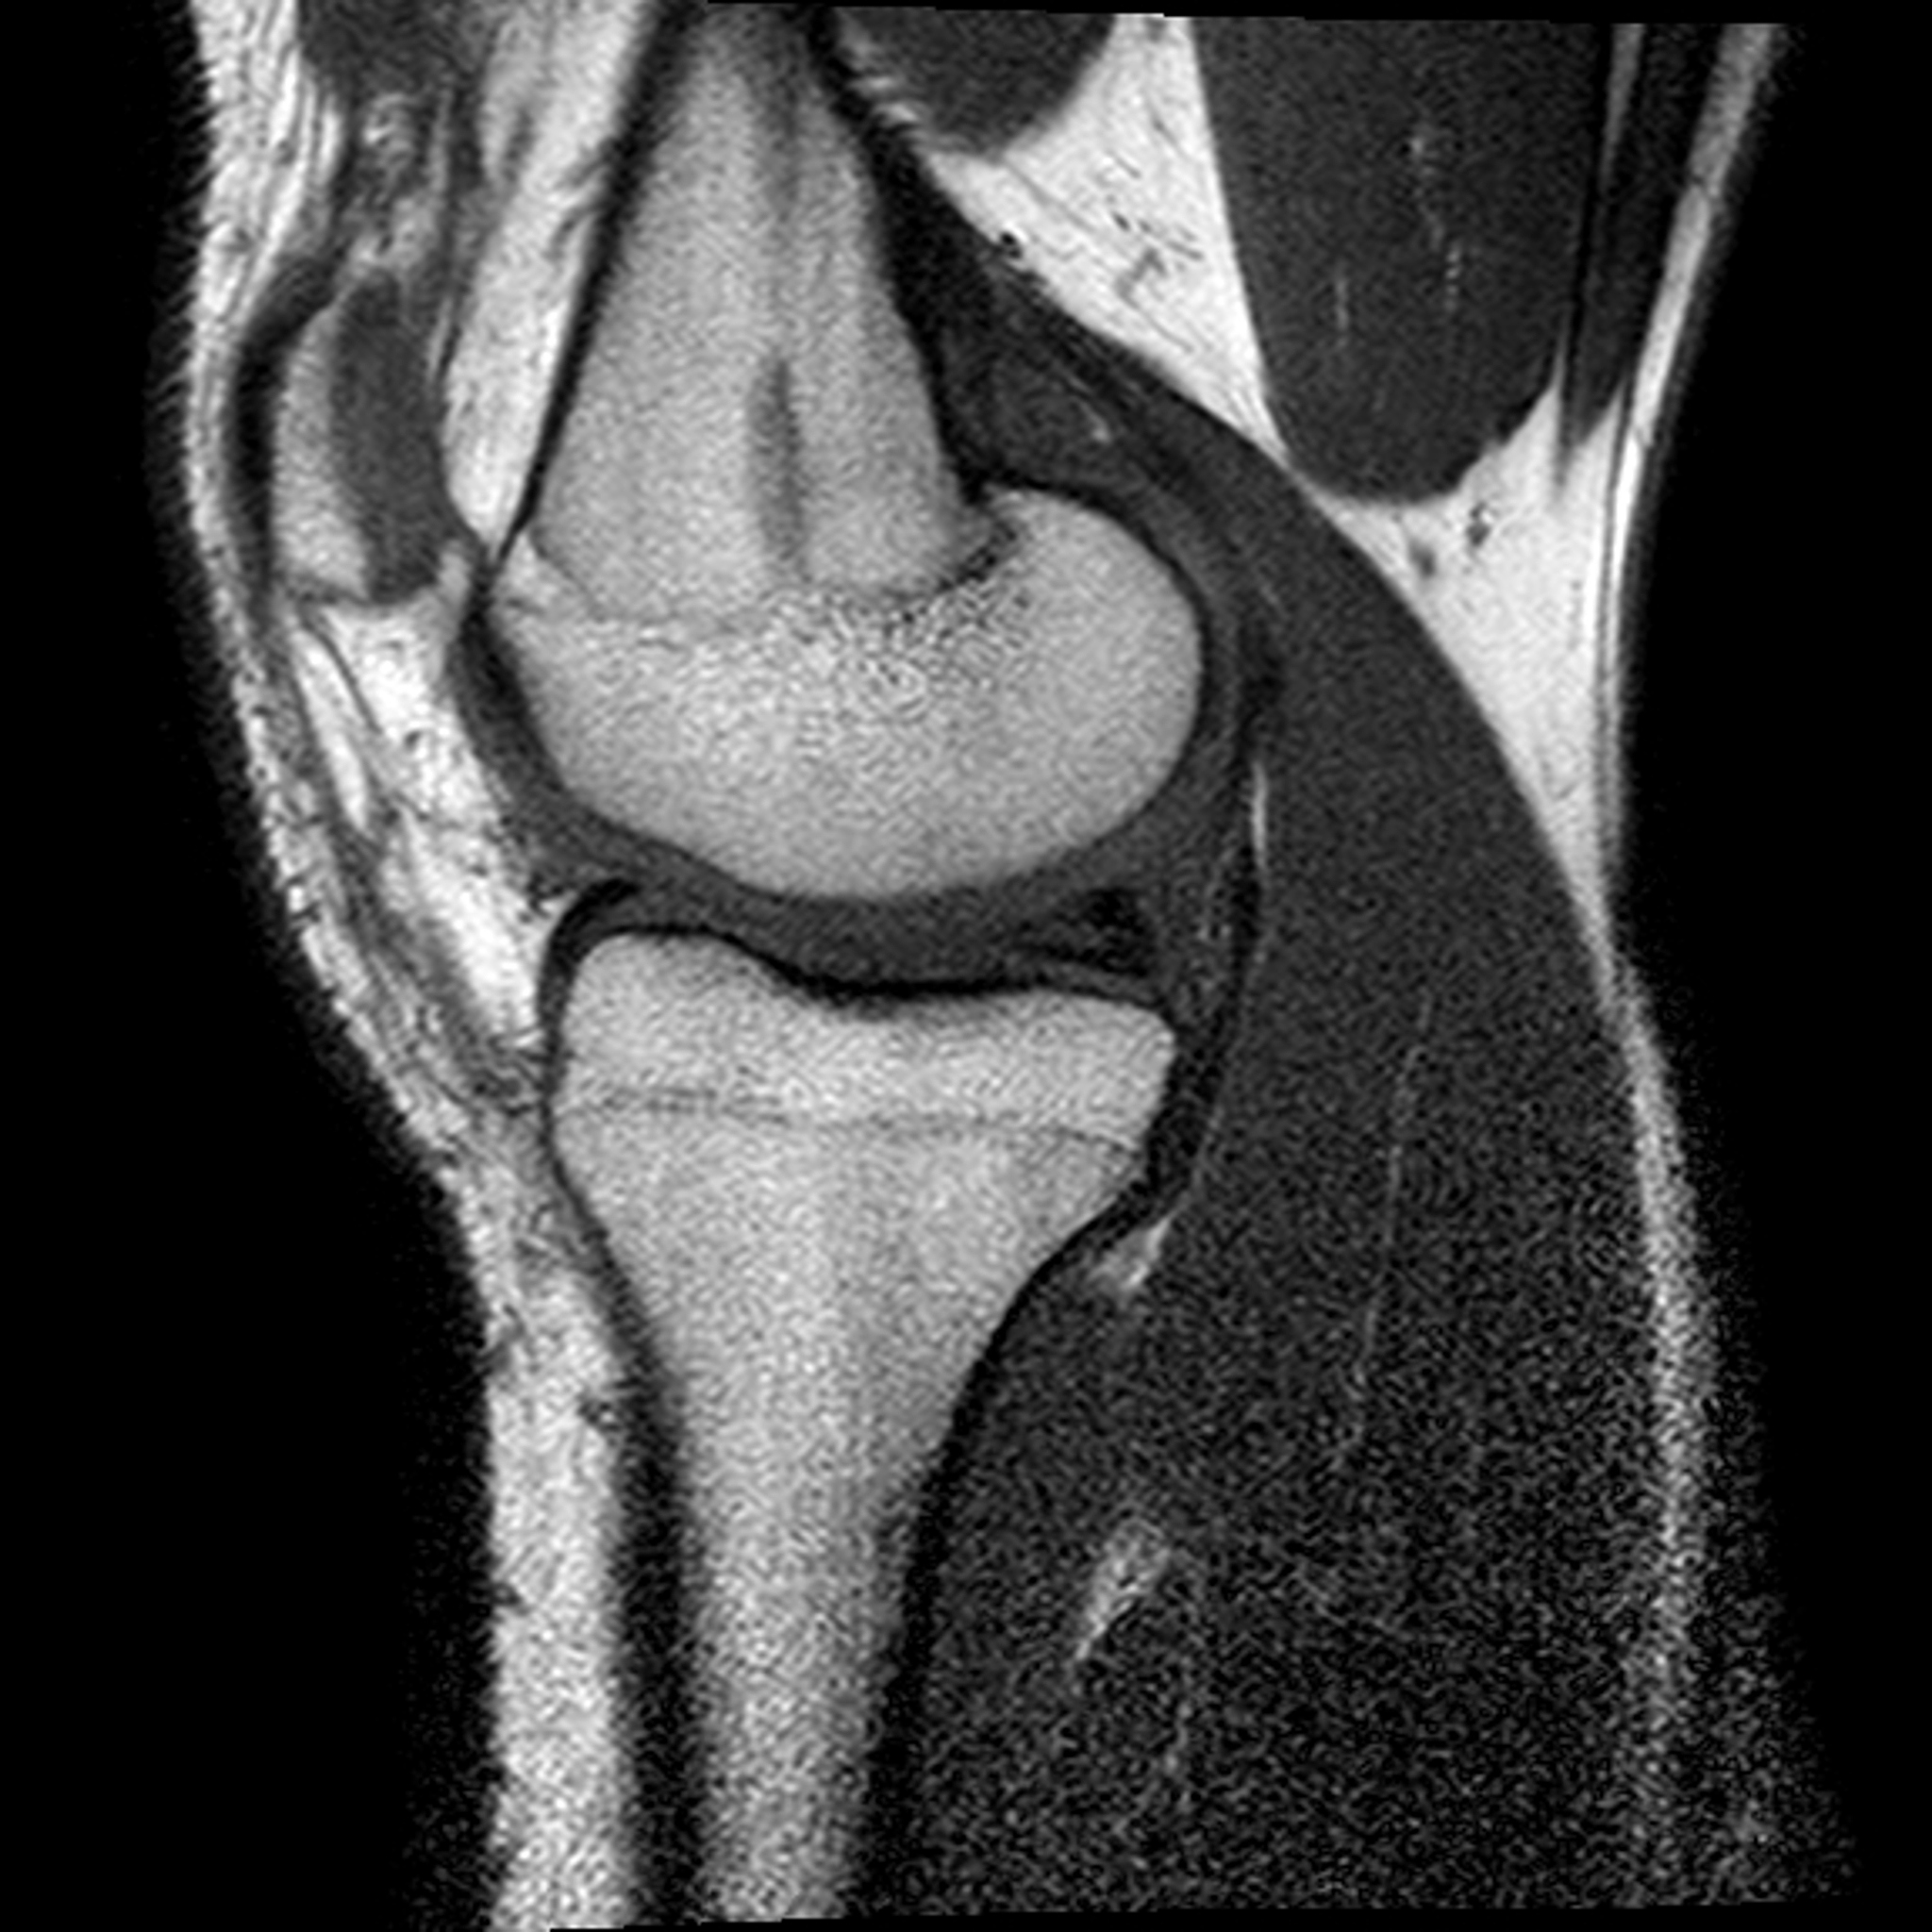

6. MRI检查:为了准确诊断后叉韧带断裂,医生可能会建议进行MRI(磁共振成像)检查。MRI可以提供详细的图像,帮助医生确定后叉韧带的断裂程度和其他可能的损伤。